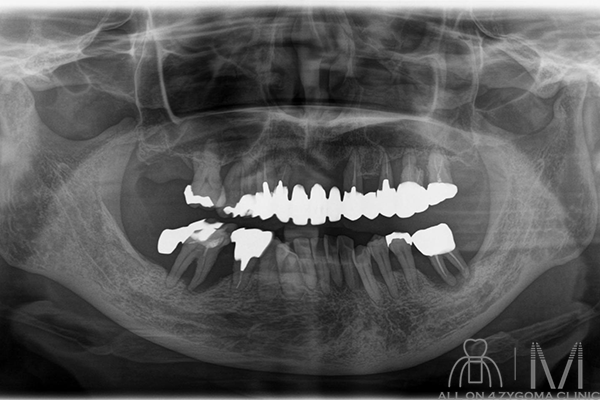

両側上顎は前臼歯歯槽骨に十分なボリュームがないが、頬側に十分なスペースの確保が見込めた。下顎は菲薄な部位はあるものの5┬5を骨整形する事で十分な骨幅の確保が見込めると判断し、この部位に4本ノーマルインプラント埋入予定とした。前歯~小臼歯部で歯槽堤の高低差が大きいことから、安定度を高めるプラットフォームの設計が必要であると考えた。また、頬骨に十分な厚みがある事からザイゴマインプラント4本を用いる上下顎All-on-4治療 を計画した。手術を円滑なものとする為、術中は静脈内鎮静法下での手術を予定した。